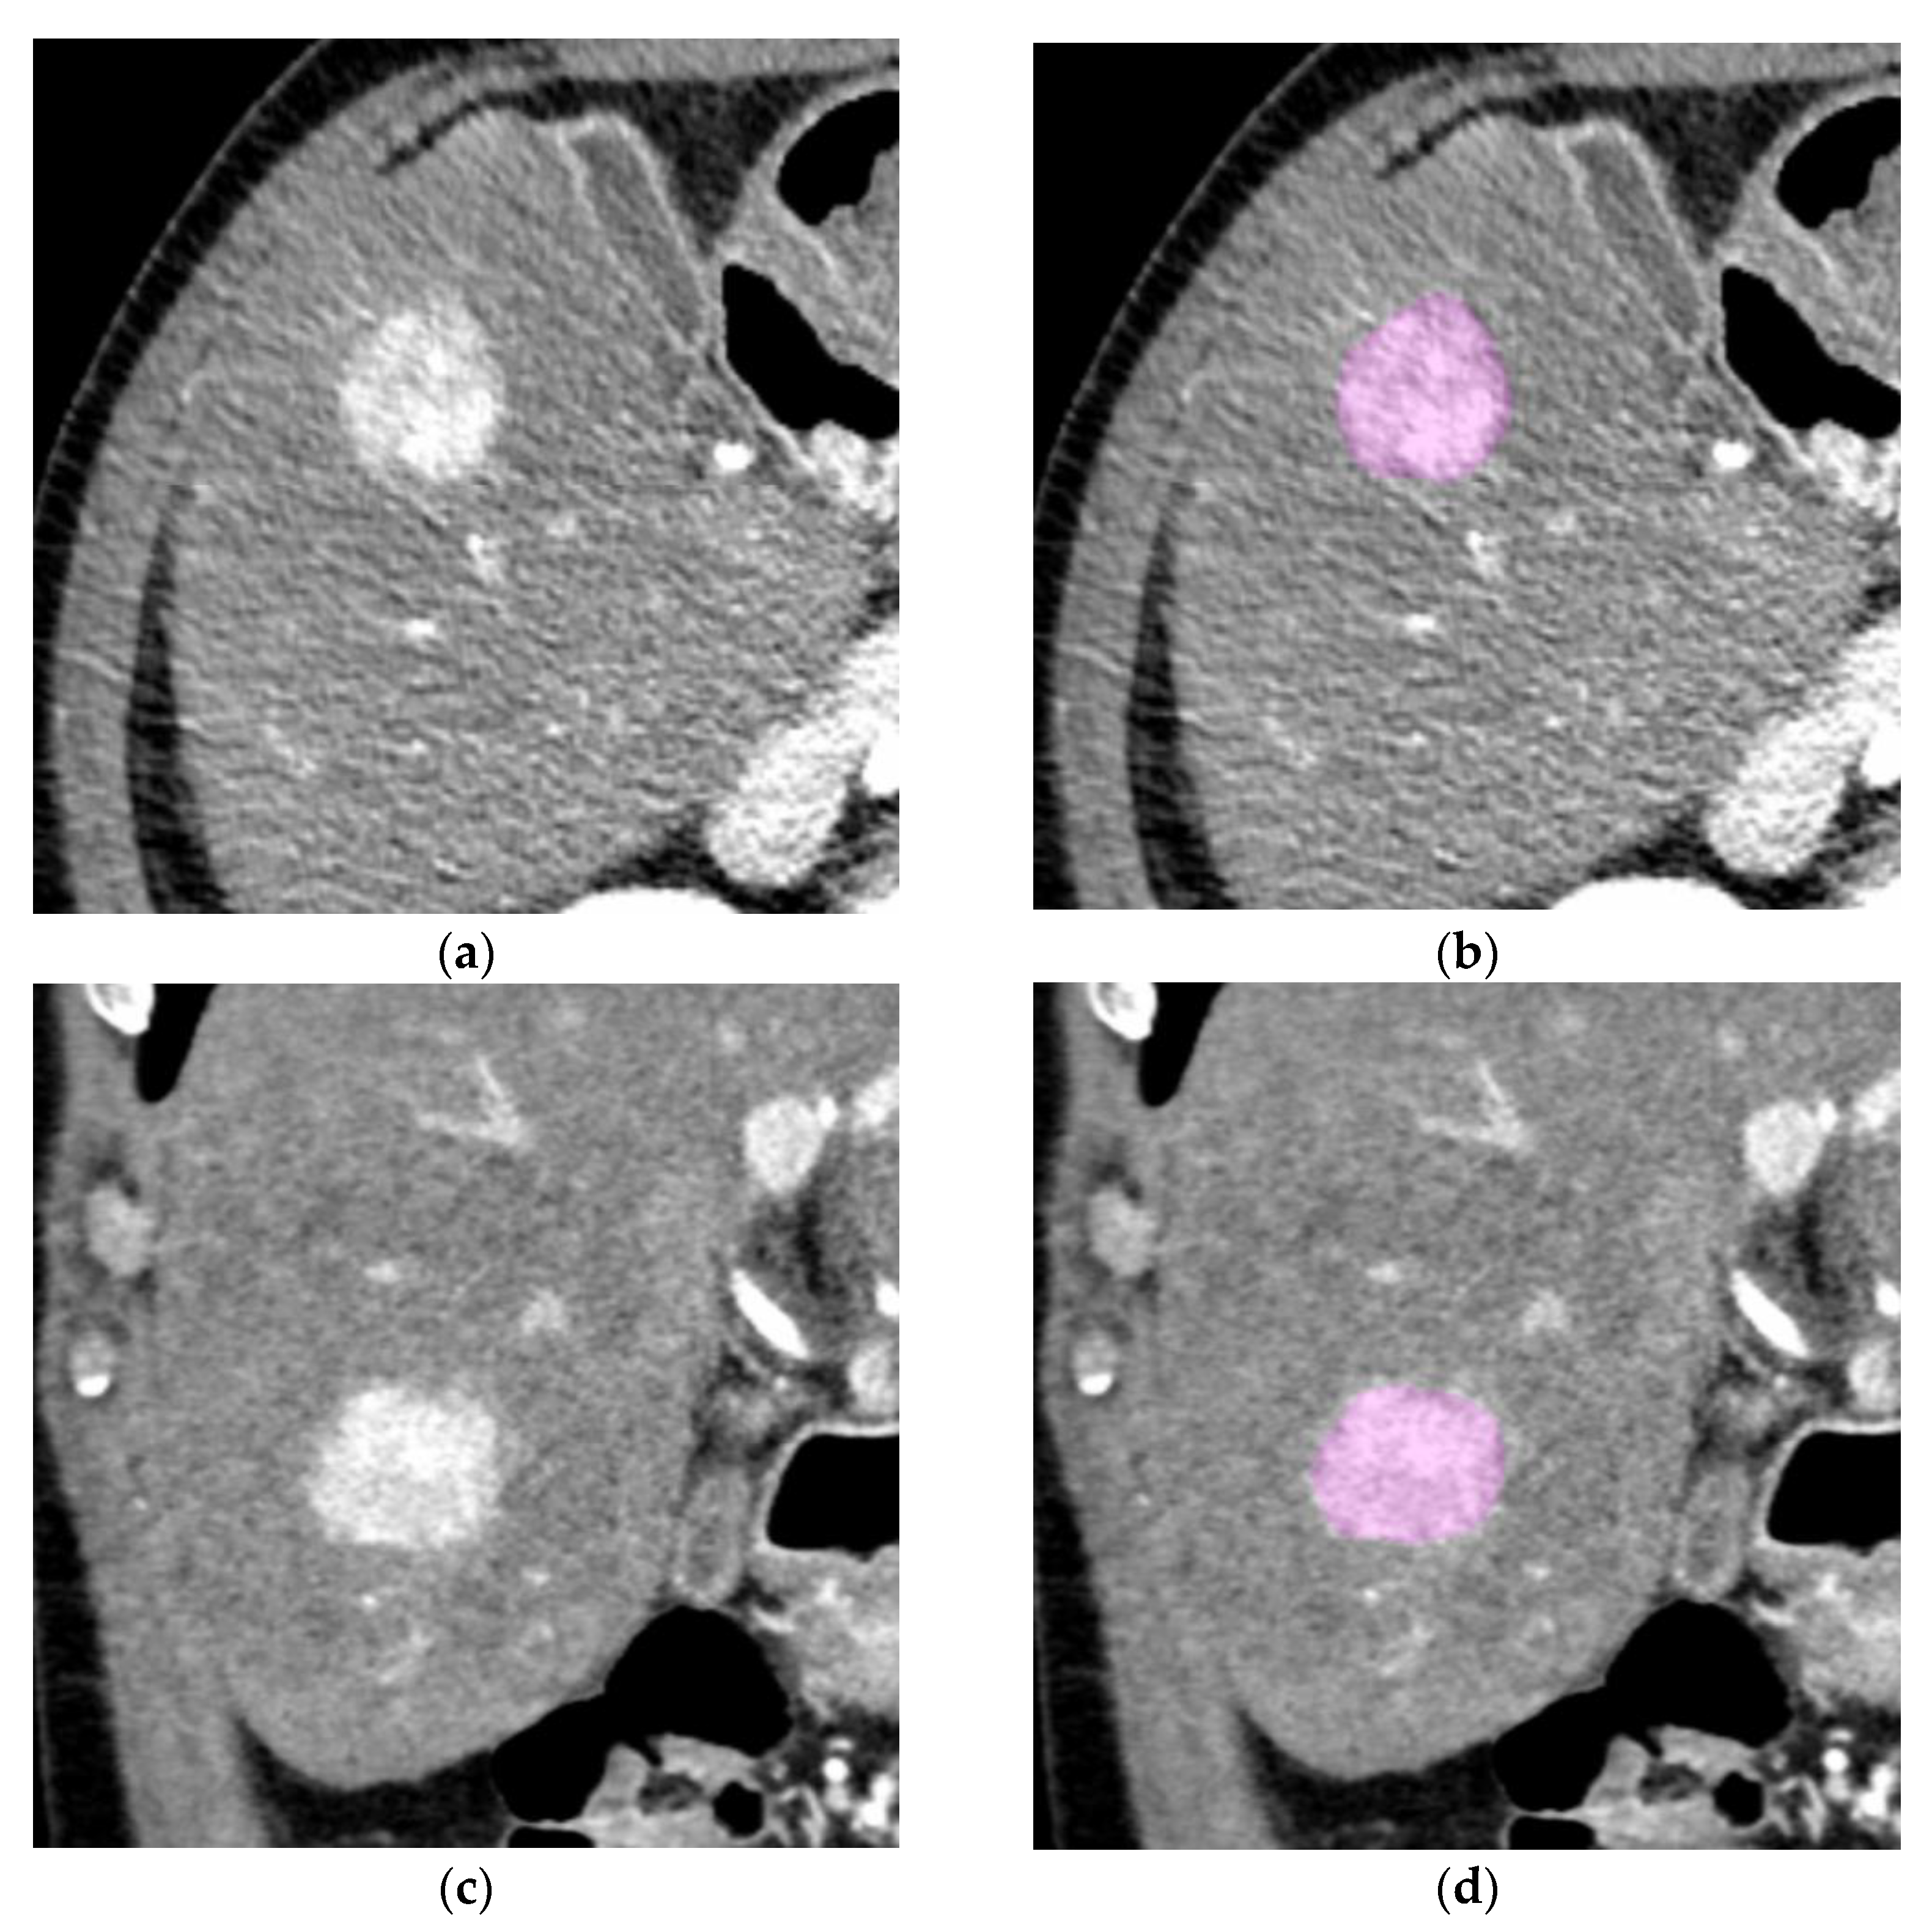

2.2. CT Examinations and Imaging Analysis

2.3. Segmentation and Texture Analysis